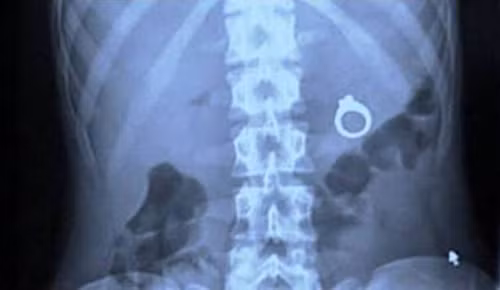

Chiếc nhẫn này nằm gọn trong ổ bụng người đàn ông đến từ New Mexico. Trong lúc cầu hôn hồi hộp, anh vô tình nuốt phải chiếc nhận ngậm sẵn trong miệng.